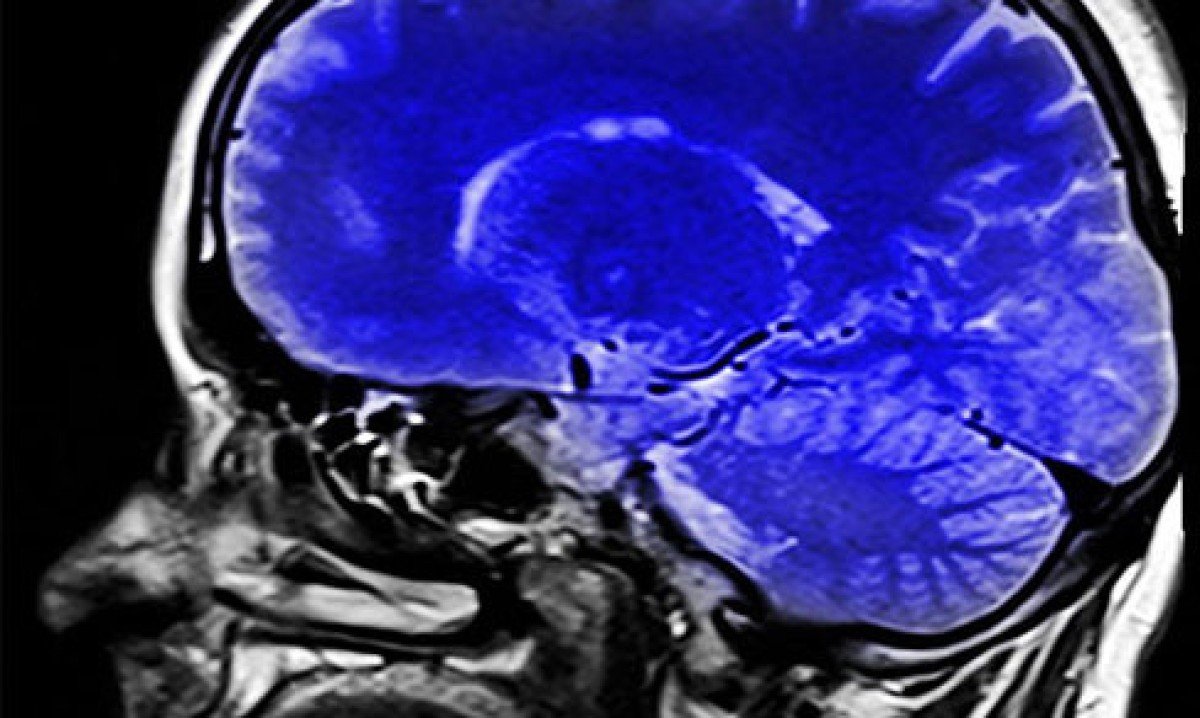

A colina é importante para que o corpo produza acetilcolina (necessária para o desenvolvimento de memória, pensamento e aprendizado), um neurotransmissor que emite as mensagens do cérebro para o corpo através das células nervosas. Foto: Imagem de Alex Dante por Pixabay -

A deficiência de colina foi associada a doenças neurodegenerativas, como o mal de Parkinson e Alzheimer. Ela é ingrediente presente em suplementos conhecidos como "nootrópicos" Foto: Freepik -